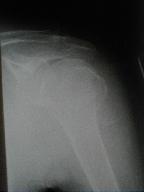

症例 9

左上腕骨骨折(頚部外転骨折)

85歳 女性

負傷年日   平成12年2月14日

負傷原因   自宅居間で肩より転倒した際負傷

2月14日受傷

上腕骨頚部骨折 その1

皮下溢血、腫脹著明で運動制限有り